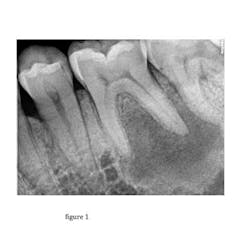

Radiographic exam

Take quality radiographs that are angulated correctly. Often two or more angles are necessary. Look for evidence of faulty restorations, caries, or changes in the PDL or periradicular radiolucent areas. This is also an opportunity to begin to appreciate the anatomy and potential complications that may arise in treatment. After radiographs are obtained, the answers to the previous questions can begin to be correlated with radiographic findings. A common error is to make a diagnosis before completing all phases of the exam.